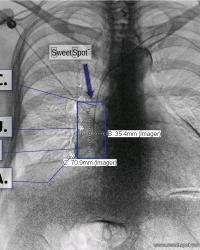

CXR Sweet Spot™ Box Measurements |